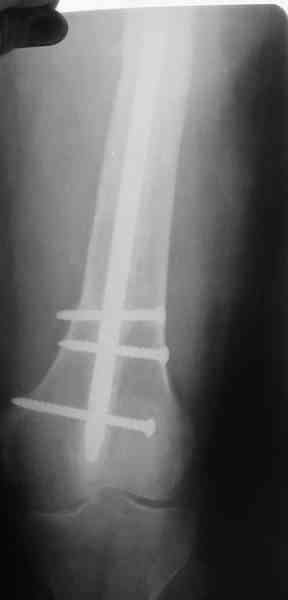

В настоящее время наш пациент ( см. http://weborto.net/forum/1177351385/) ходит с одним костылем. У него периодически открывается свищ на задне-наружной поверхности бедра с умеренным серозно-гнойным отделяемым. Температура тела и анализы нормальные. На рентгенограммах имеются признаки консолидации ложного сустава.

1, 2, 3, 4 - рентгенограммы бедра от 8 августа этого года (через четыре месяца после операции);

Вчера наш пациент был на контрольном осмотре. Вроде все идет нормально. Рентгенограммы от 25 сентября 2007 г. (прошло 5 месяцев после операции) прилагаю.